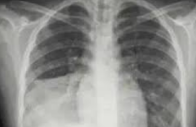

小兒支原體肺炎常年均有發病,以冬春較多,臨床以臨床起病較緩慢,主要以急性毛細支氣管炎和間質性肺炎為病理改變.支原體肺炎以發熱、劇烈咳嗽為臨床特點,易發生下呼吸道感染引發支原體肺炎,且胸部X 線征象較臨床體征明顯,也可有肺外并發癥。